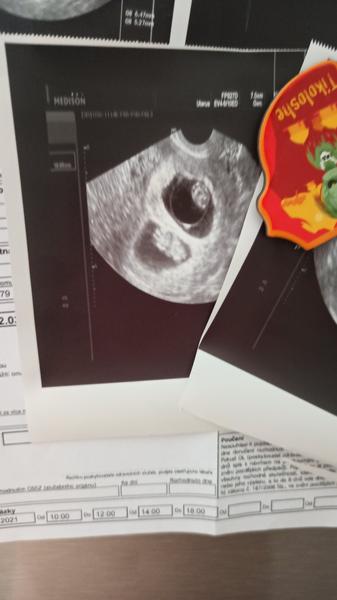

Ahoj, ja jsem brala v listopadu 1-0-1 od 5-9 a 13 DC mi doktor rekl, ze žádný folik a hned mi narval otriville? Nebo tak nejak , aby došla ms ( v přibalaku píšou, ze je na zastavení ovu, jenže ten jsem si vzala asi 3x a pak duphaston, který jsem měla doma z říjnového užívání, jelikož tamto jsem nechala v práci.) ms přišla 23dc , cykly mám treba i 50dc..doktor Na poslední kontrole po clostiku v listopadu rekl, ze uz nejsem v jeho kompetenci a ze buď se mám přestat snažit a nechat tělo, nebo jít do car a nebo čekat zazrak. Ze uz ma strach me "léčit" Ale jelikož jsem měla 1 balení navíc, tak jsem si ho v prosinci vzala 0-1-0 5-9DC a říkala jsem si, ze to stejne bude k ničemu , kdyz si dávám 1denne a ne jako minule 2. No a 8.1 test , který jsem si dělala, protože se mi událo , ze jsem tehotna .. věřím, ze to byl clostik a pro me risk byl zisk . Nyni beru utrogestan 0-0-2 do pochvy